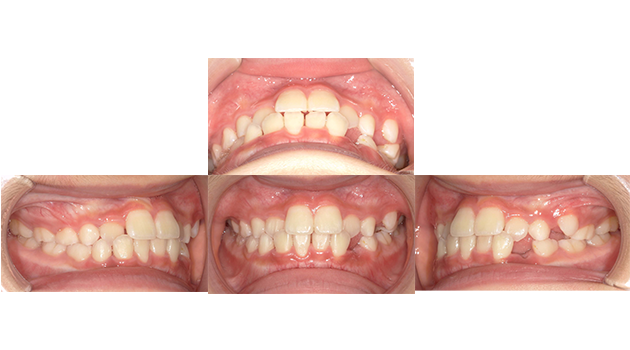

小児矯正

主訴 歯並びを治したい。

治療期間 1年半

治療費 精密検査44,000円

矯正代金385,000円

調整料金1来院につき5,500円(税込)

治療内容 歯列不正が認められたため日本矯正歯科学会認定医により、

小児矯正を行なった。

上顎前方牽引装置→ワイヤー矯正

治療のリスク リテーナーを装着しないと、

後戻りすることがある。

骨の成長発育により、2次矯正(成人矯正)が

必要になることがある。